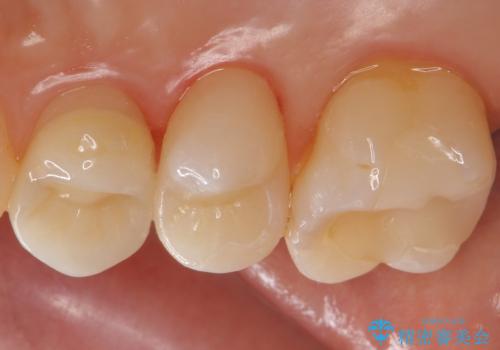

銀歯を白くしたい

- 銀の詰め物を白くしたいとのことで来院されました。

セラミックインレーでの治療を行いました。

- 右上5 セラミックインレー 77,000円×1本費用は治療当時の料金となります

残る歯の厚みが確保されている場合はインレーでの修復が可能です。